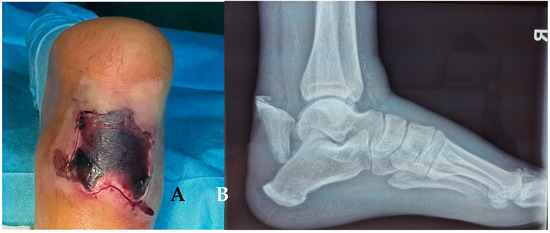

A 38-year-old male without any other comorbidities presents to the hospital following a fall (approximately 2.5 m in height). The patient complained about the pain at the level of both heels. Locally, we have identified important edema of the right foot and moderate edema of the left, spontaneous and palpatory pain at the level of both heels, and the impossibility of weight bearing. By performing X-rays and CT scans of both distal lower limbs, we have made the primary diagnosis: Bilateral calcaneal fracture, highly comminuted on the right side (Müller/AO/OTA: 82-C3) with moderate displacement and no comminution or displacement on the left side (Müller/AO/OTA: 82-A2). Figure 2. Because of the important edema, the surgery has been postponed for 7 days, during which the patient received thromboprophylaxis, pain killers, and local therapy (elevation of the limbs, local cryotherapy) while having a bilateral cast immobilization.

Figure 2. X-rays on the day of presentation in the Emergency Room (A), right calcaneus. (B) left calcaneus.